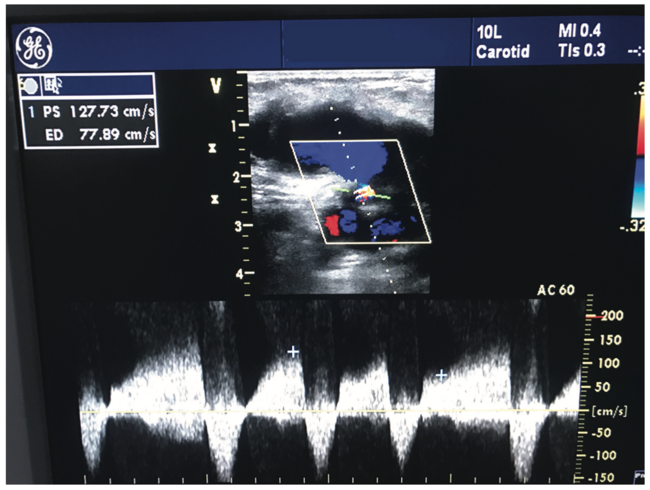

A 52-year-old hypertensive male with ongoing tobacco use presented to our outpatient clinic for regular follow-up, one and a half months after percutaneous coronary intervention via a femoral route. On inquiry, the patient complained of a swelling in the right groin. A local examination showed a pulsatile non-tender mass with normal temperature and appearance of overlying skin. There was an audible bruit with no palpable thrill. The distal limb was normal, including intact neurovascular bundle. We investigated using routine blood tests and Doppler ultrasound of affected side, which showed a large (38 mm x 45 mm), oval-shaped, blood-filled aneurysmal cavity superficial to the common femoral artery (CFA) (Figure 1). The cavity had a thin wall lined by connective tissue and linear hematoma, and was communicating with the CFA through a narrow neck (4.5 mm), all consistent with the formation of a femoral pseudoaneurysm. To confirm this diagnosis, a color Doppler at the neck was performed and showed the typical interplay of red and blue, traditionally labeled as the ‘ying-yang’ sign (Figure 2) or ‘Pepsi-Cola’ sign. Furthermore, the pulsed-wave Doppler exhibited a ‘to-and-fro’ pattern of blood flow via the neck (Figure 3). The patient was then evaluated by the interventionist and the vascular surgeon to determine how to best manage this iatrogenic complication. Options included ultrasound-guided compression, vascular surgery, and ultrasound-guided thrombin injection. The last option was selected as the appropriate first technique for treatment in this case.

Using sterile technique, two syringes each filled with 01 cc saline and thrombin were connected via a 3-way stopcock, front loaded with a 1.5-inch 22-gauge needle. Under local anesthesia, using ultrasound guidance, the needle tip was inserted into upper third of the PSA cavity (Figure 4). Once in place, the correct positioning of needle tip was confirmed first by aspiration of blood into the saline syringe and then injecting back the same, which produced intracavity bubble contrast. This was followed by the serial injection of 0.2 mL boluses of thrombin, while evaluating for thrombus formation under continuous ultrasonography (Figure 5). A total of 1 mL of thrombin was injected with immediate thrombosis in the cavity (Figure 6). The cessation of flow via the neck was confirmed by repeat PW and color Doppler at the neck (Figure 7). The patency of the distal vessels and CFA (Figure 8) was confirmed at the end of the procedure. The patient was put on bed rest for 12 hours and then mobilized. There was complete and successful thrombosis of PSA cavity without any complication. On his follow-up visit, the patient was doing well.